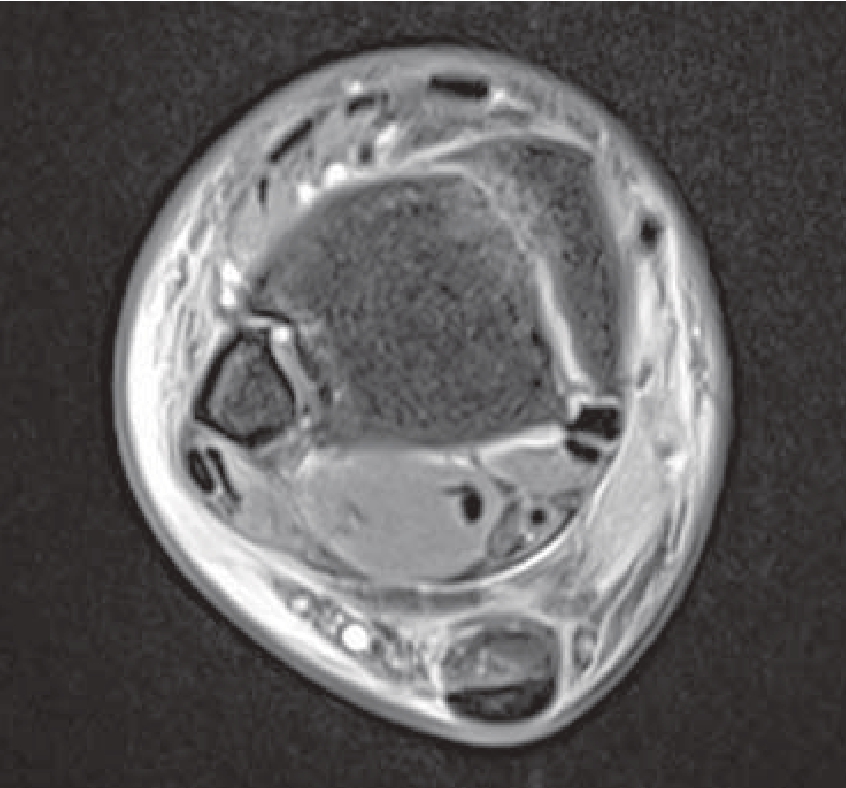

无移位或移位较小的单纯内踝骨折可采取保守治疗,对于移位较大、合并外踝、后踝骨折或下胫腓联合损伤的患者需采取手术治疗。多数内踝骨折线为横向走行,可采用1~2枚空心螺钉进行固定。而旋后内收型踝关节骨折的内踝骨折线通常为纵向走行,可采用阻挡钢板进行固定;术中需注意避免将胫骨后肌腱卡压于骨折间隙内从而影响骨折复位(图14—9);同时该型骨折常伴有胫骨远端内侧关节面的压缩骨块,关节面力线的恢复至关重要。

图14—9 旋后内收型踝关节骨折MRI显示胫骨后肌腱卡压于骨折线内